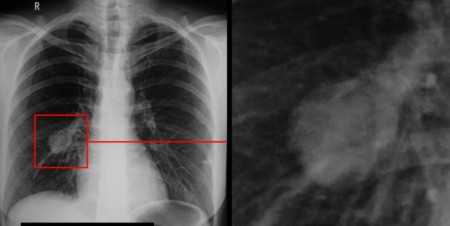

В Томске с 28 по 30 апреля пройдёт форум «Кардиология XXI века»

В Томске с 28 по 30 апреля пройдет шестой всероссийский научно-образовательный форум «Кардиология XXI века: альянсы и потенциал». В программе – более 20 секций и десять мастер-классов для кардиологов, терапевтов, реаниматологов, хирургов и медсестер.